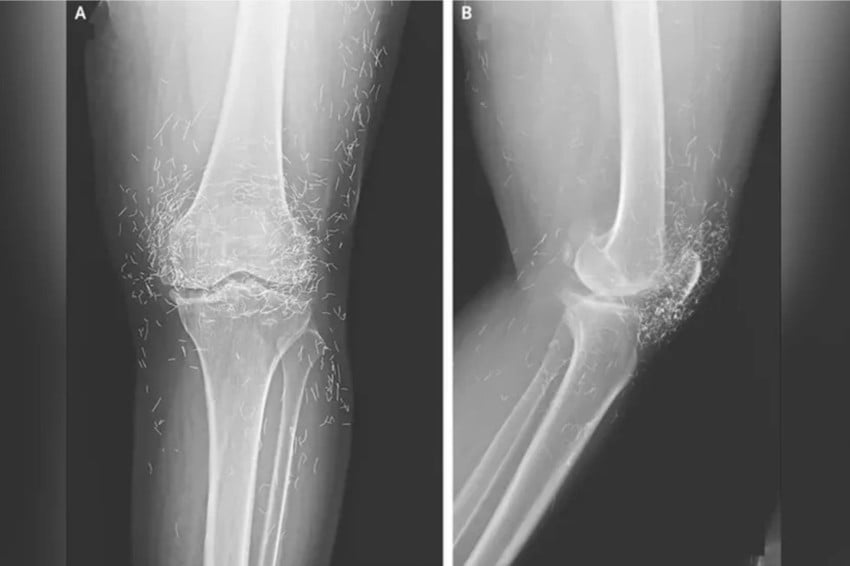

Sebuah peristiwa medis yang mengejutkan terjadi di Korea Selatan ketika tim dokter menemukan ratusan benang emas murni yang tertanam di lutut seorang pasien. Foto/Oddity Central

Dilansir dari Oddity Central, Jumat (19/9/2025), temuan ini sontak menjadi perhatian publik karena mengungkap praktik pengobatan alternatif yang tidak lazim namun masih populer di beberapa negara Asia.